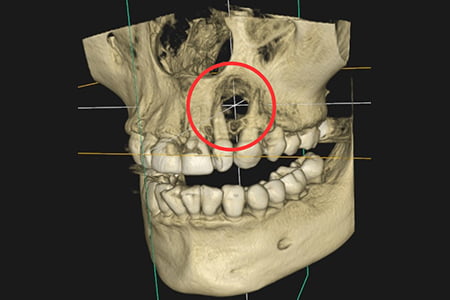

治療例3

| 症状 | 左上の前歯が急に疼く様になった |

|---|---|

| 治療方針 | 大きな骨欠損を認められる為、精密根管治療を行い骨欠損部位が改善するか経過を追う |

| 治療期間 | 10ヵ月 |

| 治療費用(税込) | ¥468,600 ※2歯分 |